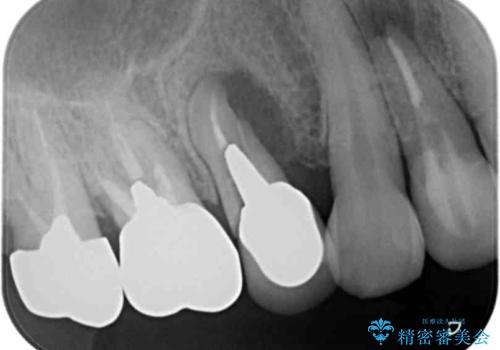

- ぐらぐらする小臼歯の治療を求めて来院されました。

X線検査、歯周組織検査より、歯は割れてしまい周囲の骨が高度に吸収してしまっている状態でした。

合わせて周囲の根尖病変や銀歯を治療するためにインプラントではなく、ご相談の上ブリッジ治療を行う治療計画としました。